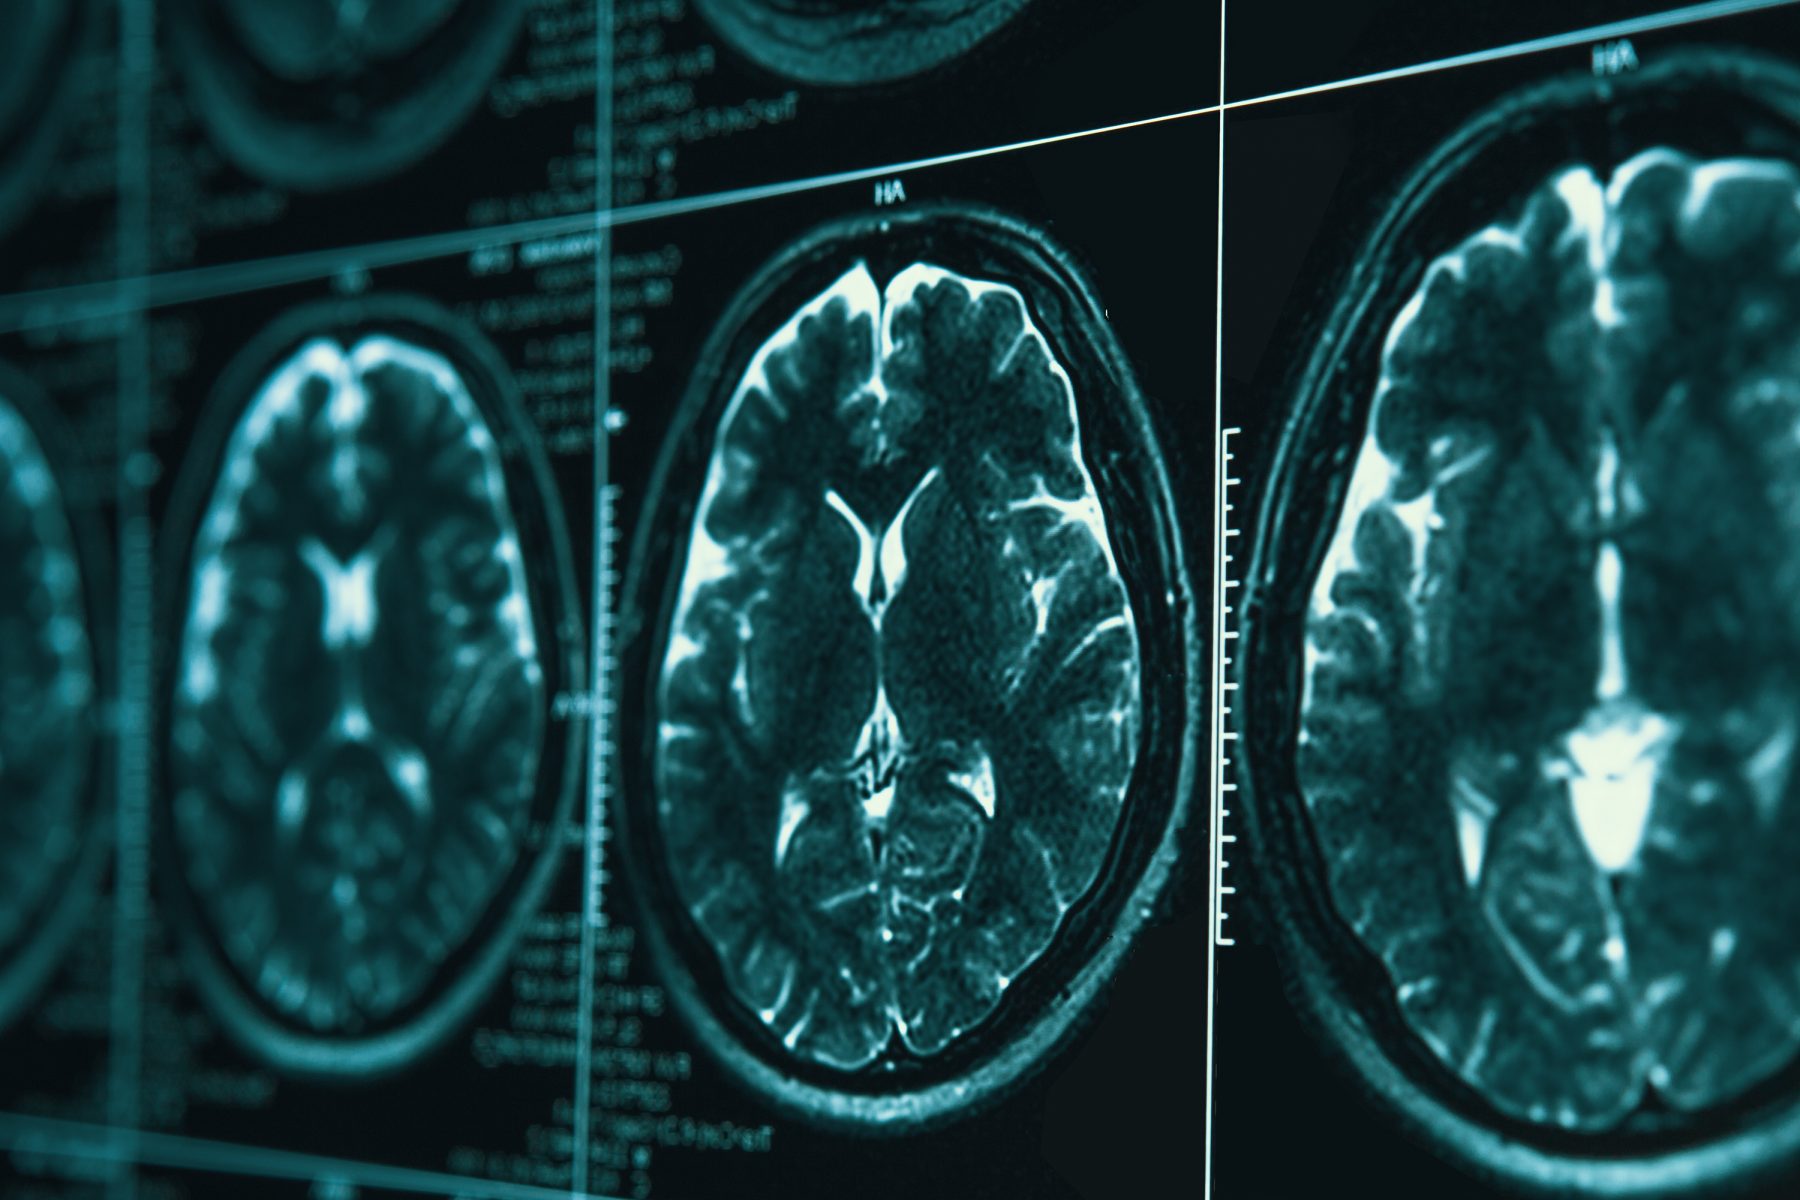

March 2026 commemorates the 20th anniversary of Cerebral Palsy and Brain Injury Awareness Month. At Thompson Smith and Puxon, we’re honouring two decades of worldwide efforts by raising awareness, combating misconceptions, advocating for inclusion for people living with Cerebral Palsy and Brain Injury.

Cerebral Palsy is an umbrella term used to describe a group of disorders caused by non-progressive brain abnormality that results in difficulty with movement, tone, or posture. The abnormal development or damage to parts of the brain controlling movement that occurs prenatally, during birth or postnatally, is known as congenital Cerebral Palsy.

The main risk factors of congenital Cerebral Palsy are prematurity and low birth weight. Other causes can include stroke, infections and lack of oxygen to the brain.

Cerebral Palsy can also occur whilst the brain is developing in the first few years of life, namely acquired Cerebral Palsy. Acquired Cerebral Palsy is usually associated with an infection, such as meningitis, or a head injury. However, there are many cases of Cerebral Palsy worldwide where the exact cause is not known and each individual patient will often have their own multifactorial aetiology.